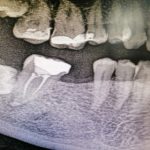

El primer paso en una situación así es realizar un estudio radiográfico para analizar la situación en el estado actual de la boca. En ese estudio pudimos observar que la mejor propuesta de tratamiento, para su caso concreto, era la colocación de implantes como vía para reponer las piezas dentales ausentes.